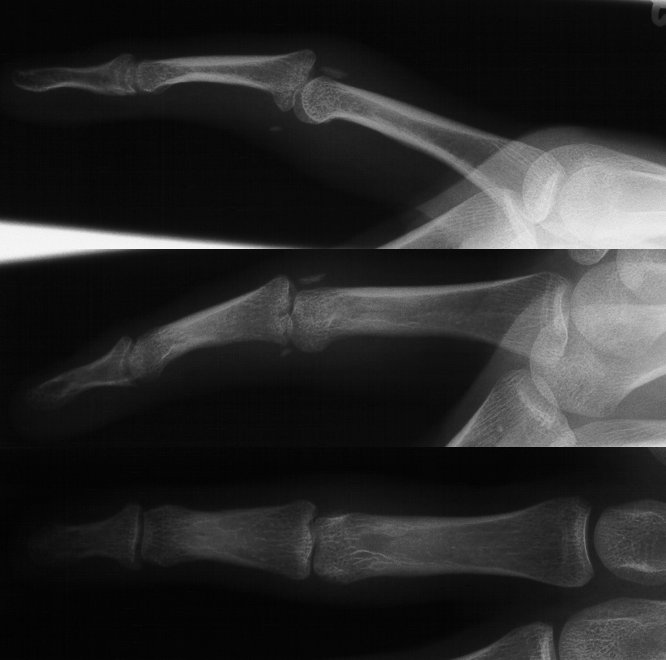

Xrays show a comminuted dorsal fracture dislocation of the proximal interphalangeal joint with dorsal subluxation.

The joint moves, but through an unnatural hinging on the edge of the fracture.